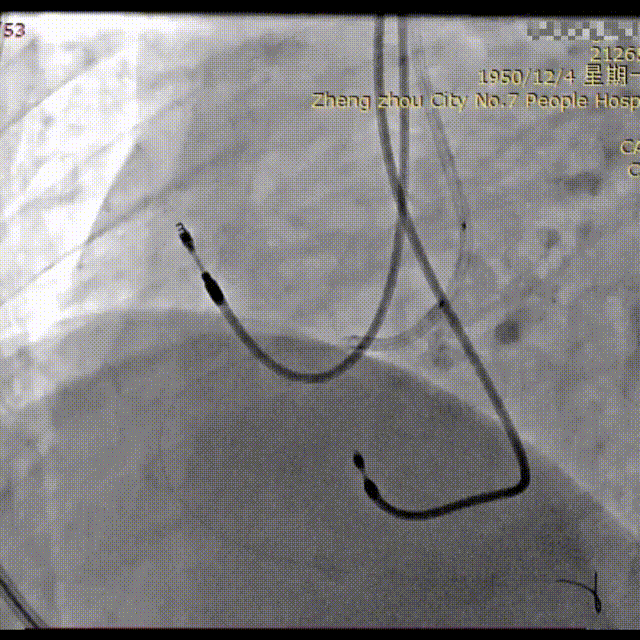

手术过程概览:

冠脉造影